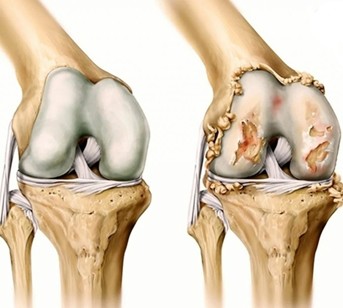

Что происходит в суставе

Коленный сустав образован бедренной и большеберцовой костями, покрытыми гиалиновым хрящом, а также менисками, связками и синовиальной оболочкой.

Хрящ выполняет роль амортизатора и обеспечивает плавное скольжение суставных поверхностей.

При гонартрозе:

• хрящ истончается и теряет эластичность

• ухудшается питание (трофика) тканей

• увеличивается трение между костями

• формируются костные разрастания (остеофиты)

• развивается воспаление (синовит)

В результате нарушается нормальная биомеханика сустава и появляется боль.

1 стадия (начальная)

• незначительные изменения суставного хряща

• боль возникает только при нагрузке

• отсутствует выраженная деформация

• функция сустава сохранена

2 стадия (умеренная)

• истончение и частичное разрушение хряща

• формирование остеофитов

• боль при обычной повседневной активности

• умеренная скованность, особенно после покоя

• частичное ограничение движений

3 стадия (выраженная)

• значительное разрушение хряща

• деформация сустава

• постоянная боль (в том числе в покое)

• выраженное ограничение подвижности

• возможна хромота

4 стадия (тяжёлая)

• практически полное разрушение хряща

• резкая деформация сустава

• интенсивная постоянная боль

• почти полная утрата подвижности

• значительное нарушение функции конечности (вплоть до инвалидизации)